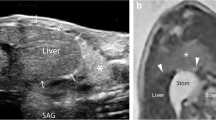

Three-dimensional model development

Two models, with identical diaphragmatic defects, were designed and built to simulate the operative steps of CDH repair via laparotomy and thoracoscopy with assessment of interobserver reliability of measuring the defect. Parental informed consent was obtained to use a pre-existing MRI scan from a foetus with a prenatal diagnosis of CDH for the purposes of designing a surgical simulation model. Stereolithography (STL) files were created from the patient MRI using the open-source software ITK-SNAP (v.3.8.0, www.itksnap.org). The size and relative proportions of the thorax, diaphragm and defect were delineated and segmented. The computer-assisted design (CAD) software Blender 3D (Blender Foundation, USA) and Fusion 360 (Autodesk Inc, USA) were used to clean, refine, and modify the ribcage, spine and pelvis.

Using measurements derived from the foetal MRI, moulds for silicone casting of soft organs and tissues were 3D-printed, including diaphragm, lung, liver, spleen and bowel. Platinum-catalysed silicone (Smooth-On Inc., Pennsylvania, United States) of varying hardness, and dyed with pigment, was used to maximise realism. The silicone components were applied to the 3D-printed model (Fig. 1). The silicone diaphragm was constructed based on measurements from the patient MRI. These measurements were replicated in the CAD software to create a diaphragm measuring 42 mm by 75 mm (Fig. 2), therefore, each hemi-diaphragm measured 42 mm by 37.5 mm. The entire diaphragm was used in the model of repair via laparotomy and the left hemi-diaphragm was used in the thoracoscopic repair. The defect was measured on the MRI and was added to the silicone diaphragm after curing. This measured 15 mm by 15 mm.